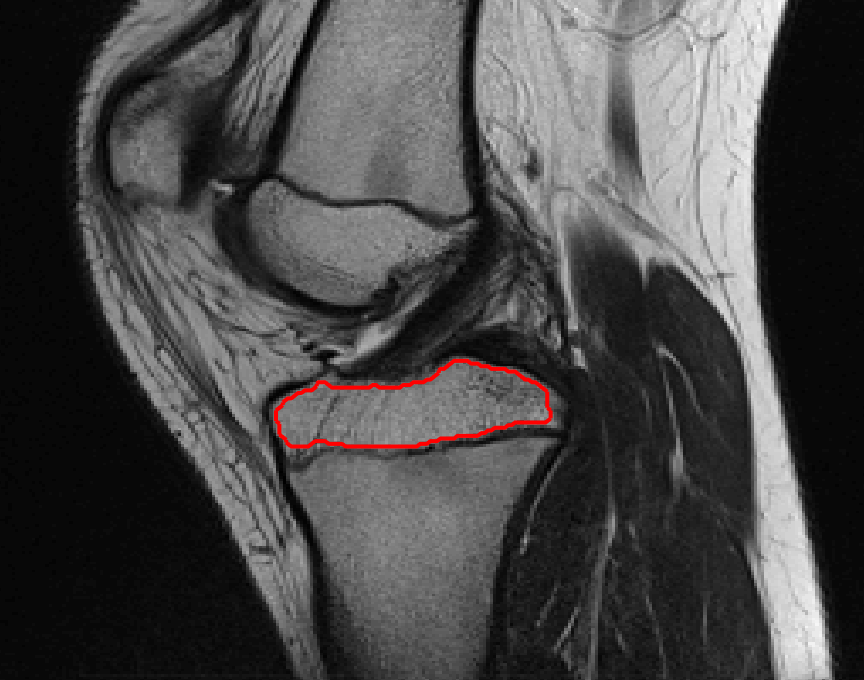

Four sets of test results are shown below. In Test 1 we compare models M1 – M6 to the proposed model M7 for two images which are hard to segment. The first is a CT scan from which we would like to segment the lower portion of the heart, the second is an MRI scan of a knee and we would like to segment the top of the Tibia. See Figure 9 for the test images and the marker sets used in the experiments. In Test 2 we will review the sensitivity of the proposed model to the main parameters. In Test 3 we will give several results achieved by the model using marker and anti-marker sets. In Test 4 we show the initialisation independence and marker independence of the Geodesic Model on real images.

In this test we give the segmentation results for models M1 – M7 for the two challenging test images shown in Figure 9. The marker and anti-marker sets used in the experiments are also shown in this figure. After extensive parameter tuning, the best final segmentation results for each of the models are shown in Figures 10 and 11. For M1 – M4 we obtain incorrect segmentations in both cases. In particular, the results of M2 and M4 are interesting as the former gives poor results for both images, and the latter gives a reasonable result for Test Image 1 and a poor result for Test Image 2. In the case of M2, the regularisation term includes the edge detector and the distance penalty term (see (4)). It is precisely this which permits the poor result in Figures 10(b) and 11(b) as the edge detector is zero along the contour and the fitting terms are satisfied there (both intensity and area constraints) – the distance term is not large enough to counteract the effect of these. In the case of M4, the distance term and edge detector are separated from the regulariser and are used to weight the Chan-Vese fitting terms (see (9)). The poor segmentation in Figure 11(b) is due to the Chan-Vese terms encouraging segmentation of bright objects (in this case), weighting enforces these terms at all edges in the image and near . In experiments, we find that M4 performs well when the object to segment is of approximately the highest or lowest intensity in the image, however when this is not the case, results tend to be poor. We see that, in both cases, models M5 and M6 give much improved results to M2 and M4 (obtained by incorporating the geodesic distance penalty into each). The proposed Geodesic Model M7 gives an accurate segmentation in both cases. It remains to compare M5, M6 and M7. We see that M5 is a non-convex model (and cannot be made convex [39]), therefore results are initialisation dependent. It also requires one more parameter than M6 and M7, and an accurate set to give a reasonable area constraint in (4). These limitations lead us to conclude M6 and M7 are better choices than M5. In the case of M6, it has the same number of parameters as M7 and gives good results. M6 can be viewed as the model M7 with weighted intensity fitting terms (compare (18) and (30)). Experimentally, we find that the same quality of segmentation result can be achieved with both models generally, however M6 is more parameter sensitive than M7. This can be seen in the parameter map in Figure 12 with M7 giving an accurate result for a wider range of parameters than M6. To show the improvement of M7 over previous models, we also give an image in Figure 13 which can be accurately segmented with M7 but the correct result is never achieved with M6 (or M3). Therefore we find that M7 outperforms all other models tested M1 – M6.

(i) (ii) (iii) (iv)